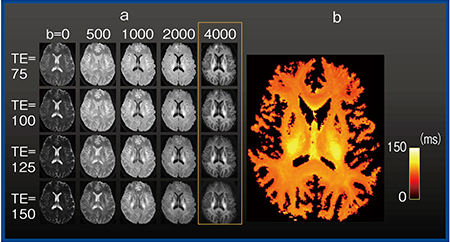

4.画像提示

図3は,Vantage Galan 3Tで撮像した実際の画像であるが,前述のとおり,b値だけでなくTEも変化させながらNODDI的な撮像を複数回行っている(a)。TEが長くb値が高いものほどノイズの影響が強くなるが,提示している範囲のb-TEでは解析に耐えそうな画像が取得できている。

McKinnonらが報告した手法10)を用いて,軸索内のT2値を計算した(図3 b)。軸索内のT2値を定量できているのだとすれば,神経変性疾患において組織の特徴により特異的に迫れる可能性があり興味深い。

図3 Vantage Galan 3Tにおけるパラメータの設定範囲の拡大

a:b値およびTEを変化させた画像

b:intra-axonal compartmentのT2 10)